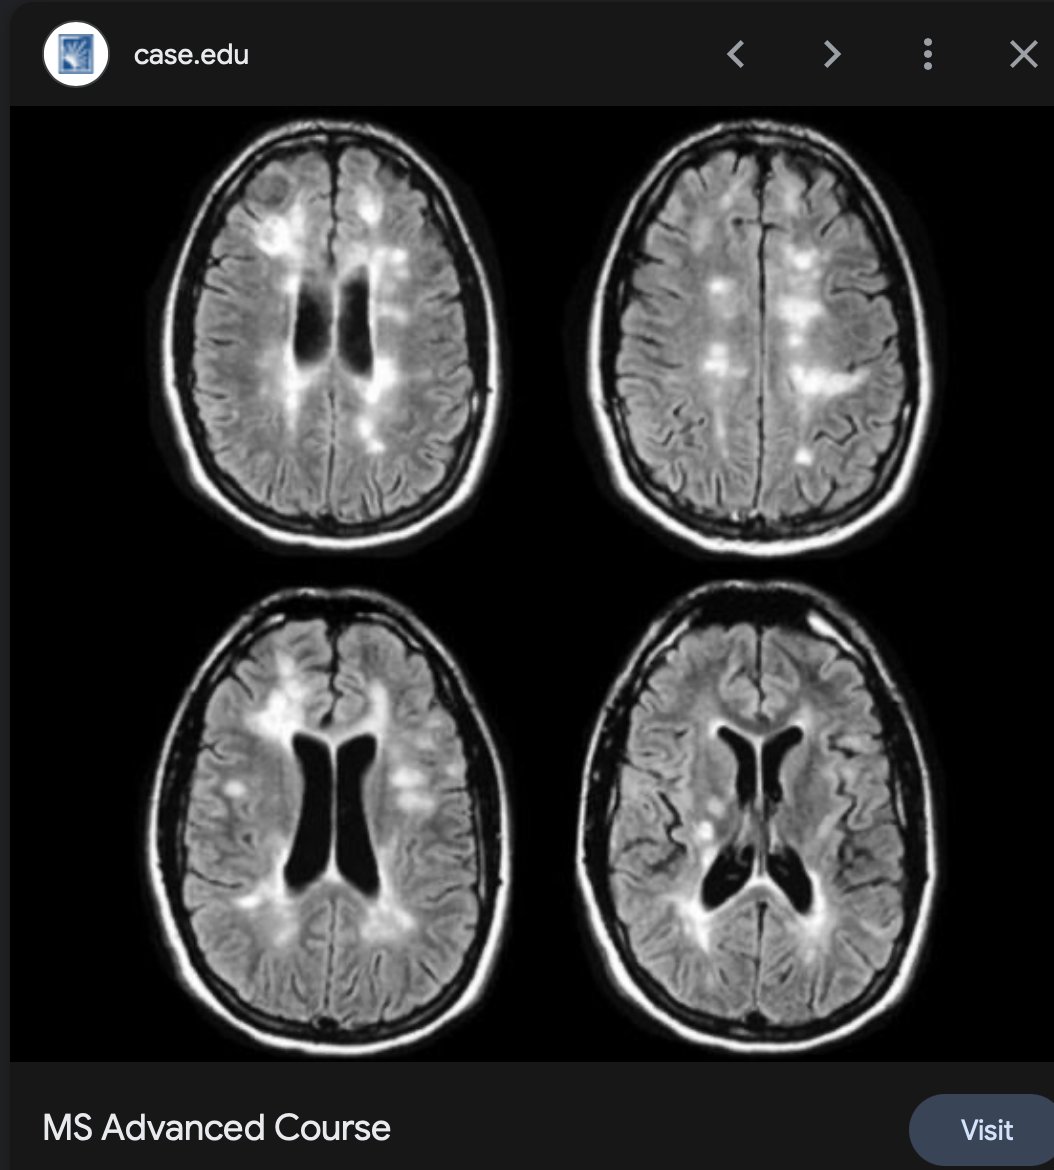

Melanin Destruction: If the system determines it cannot win the fight against this chemical load, the MITF-AMPAR signal might trigger the shutdown of melanin production as a form of biological "triage," explaining the white-matter changes and sensory processing issues seen in post-inoculation syndromes.